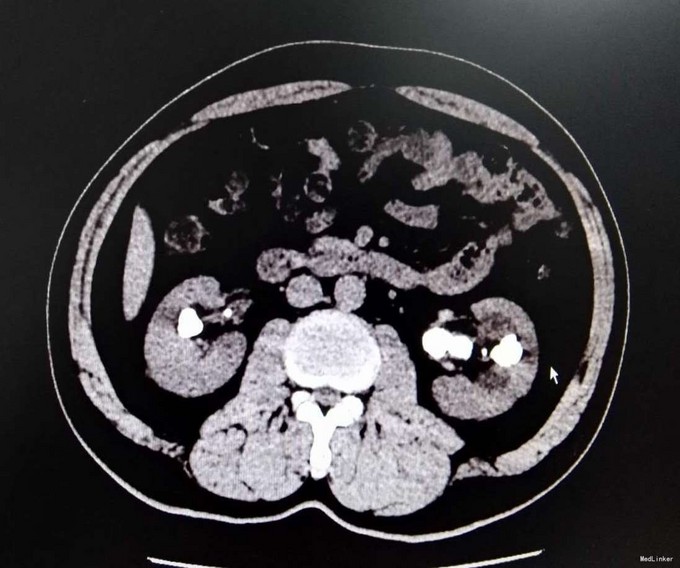

3、查体:未见明显阳性体征 4、辅助检查:外院平片:双肾多发结石;我院CTU:双肾多发结石,左侧肾盂输尿管连接处结石,并双肾积水,左肾明显,双侧肾盂、输尿管炎症。

5、诊断:肾结石(双肾多发结石) 6、治疗:入院后完善相关检查,双肾CTU:双肾多发结石,左侧肾盂输尿管连接处结石,并双肾积水,左肾明显,双侧肾盂、输尿管炎症。排除手术禁忌症后行左侧PCNL术,术后恢复良好,拔出肾造瘘管后,先出院休息,2周后返院进一步治疗